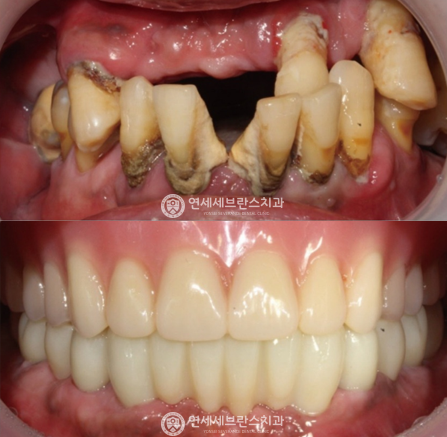

03

전악 임플란트

치아가 하나도 없거나 심각한 구강질환을 앓고 있어도

전악 보철을 제작, 임플란트를 치조골에 식립해

기능적, 심미적으로 자연치아와 가장 유사한 수준으로 재현이 가능합니다.